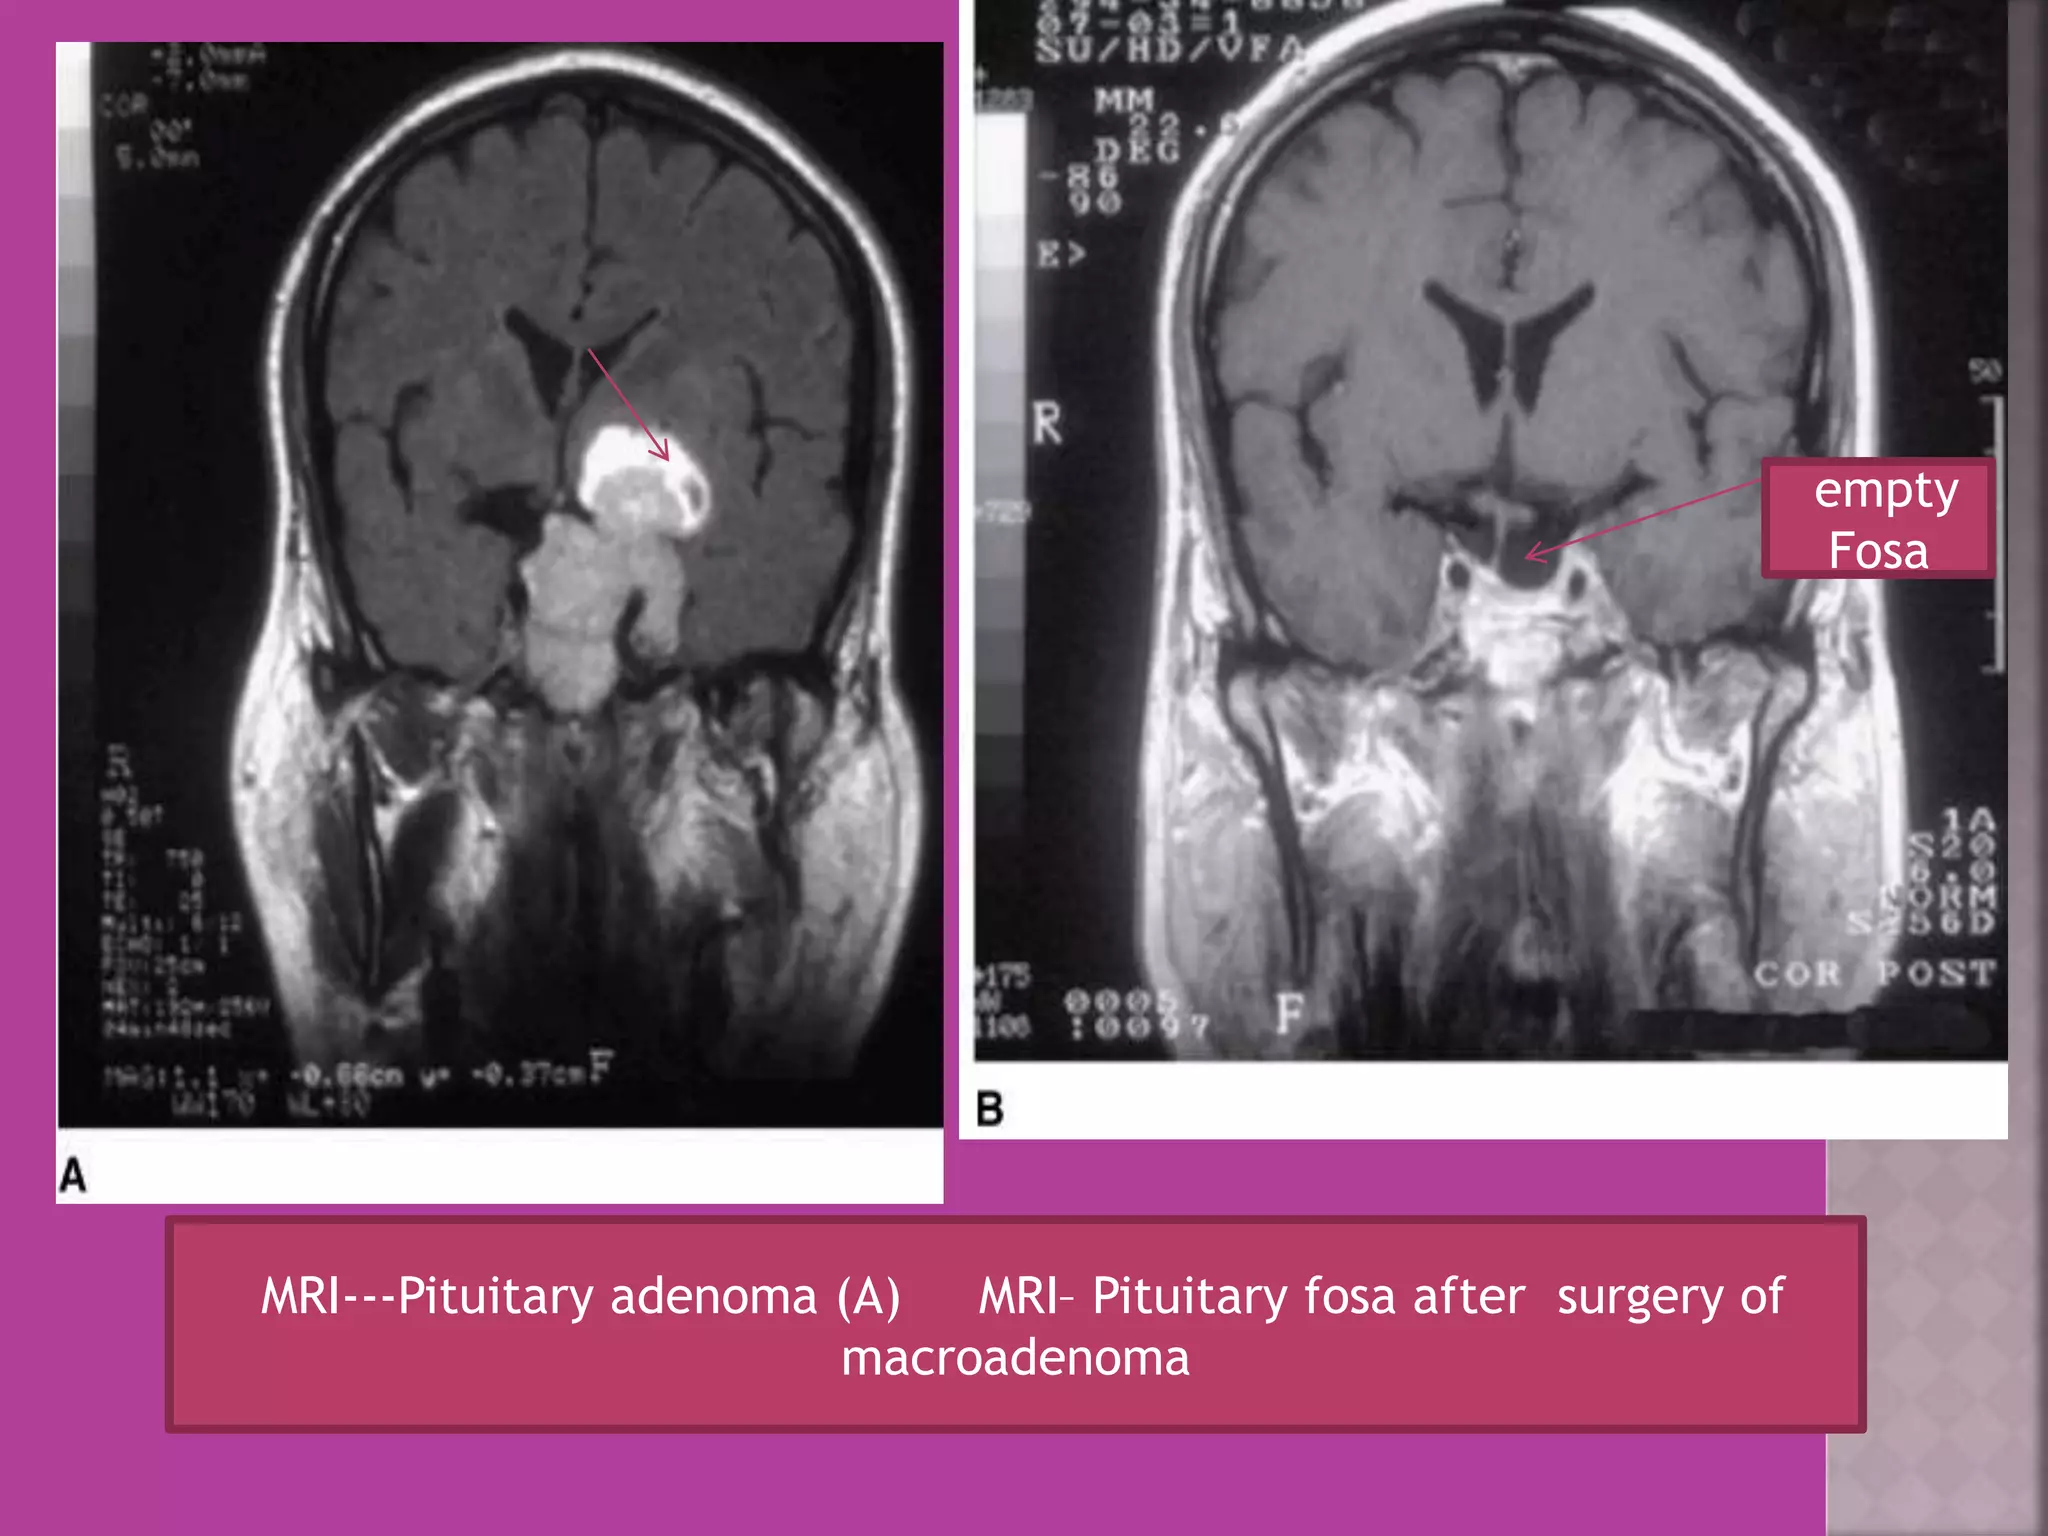

MRI---Pituitary adenoma (A) MRI– Pituitary fosa after surgery of

macroadenoma

empty

Fosa

MRI---Pituitary adenoma (A)MRI– Pituitary fosa after surgery of macroadenoma empty Fosa